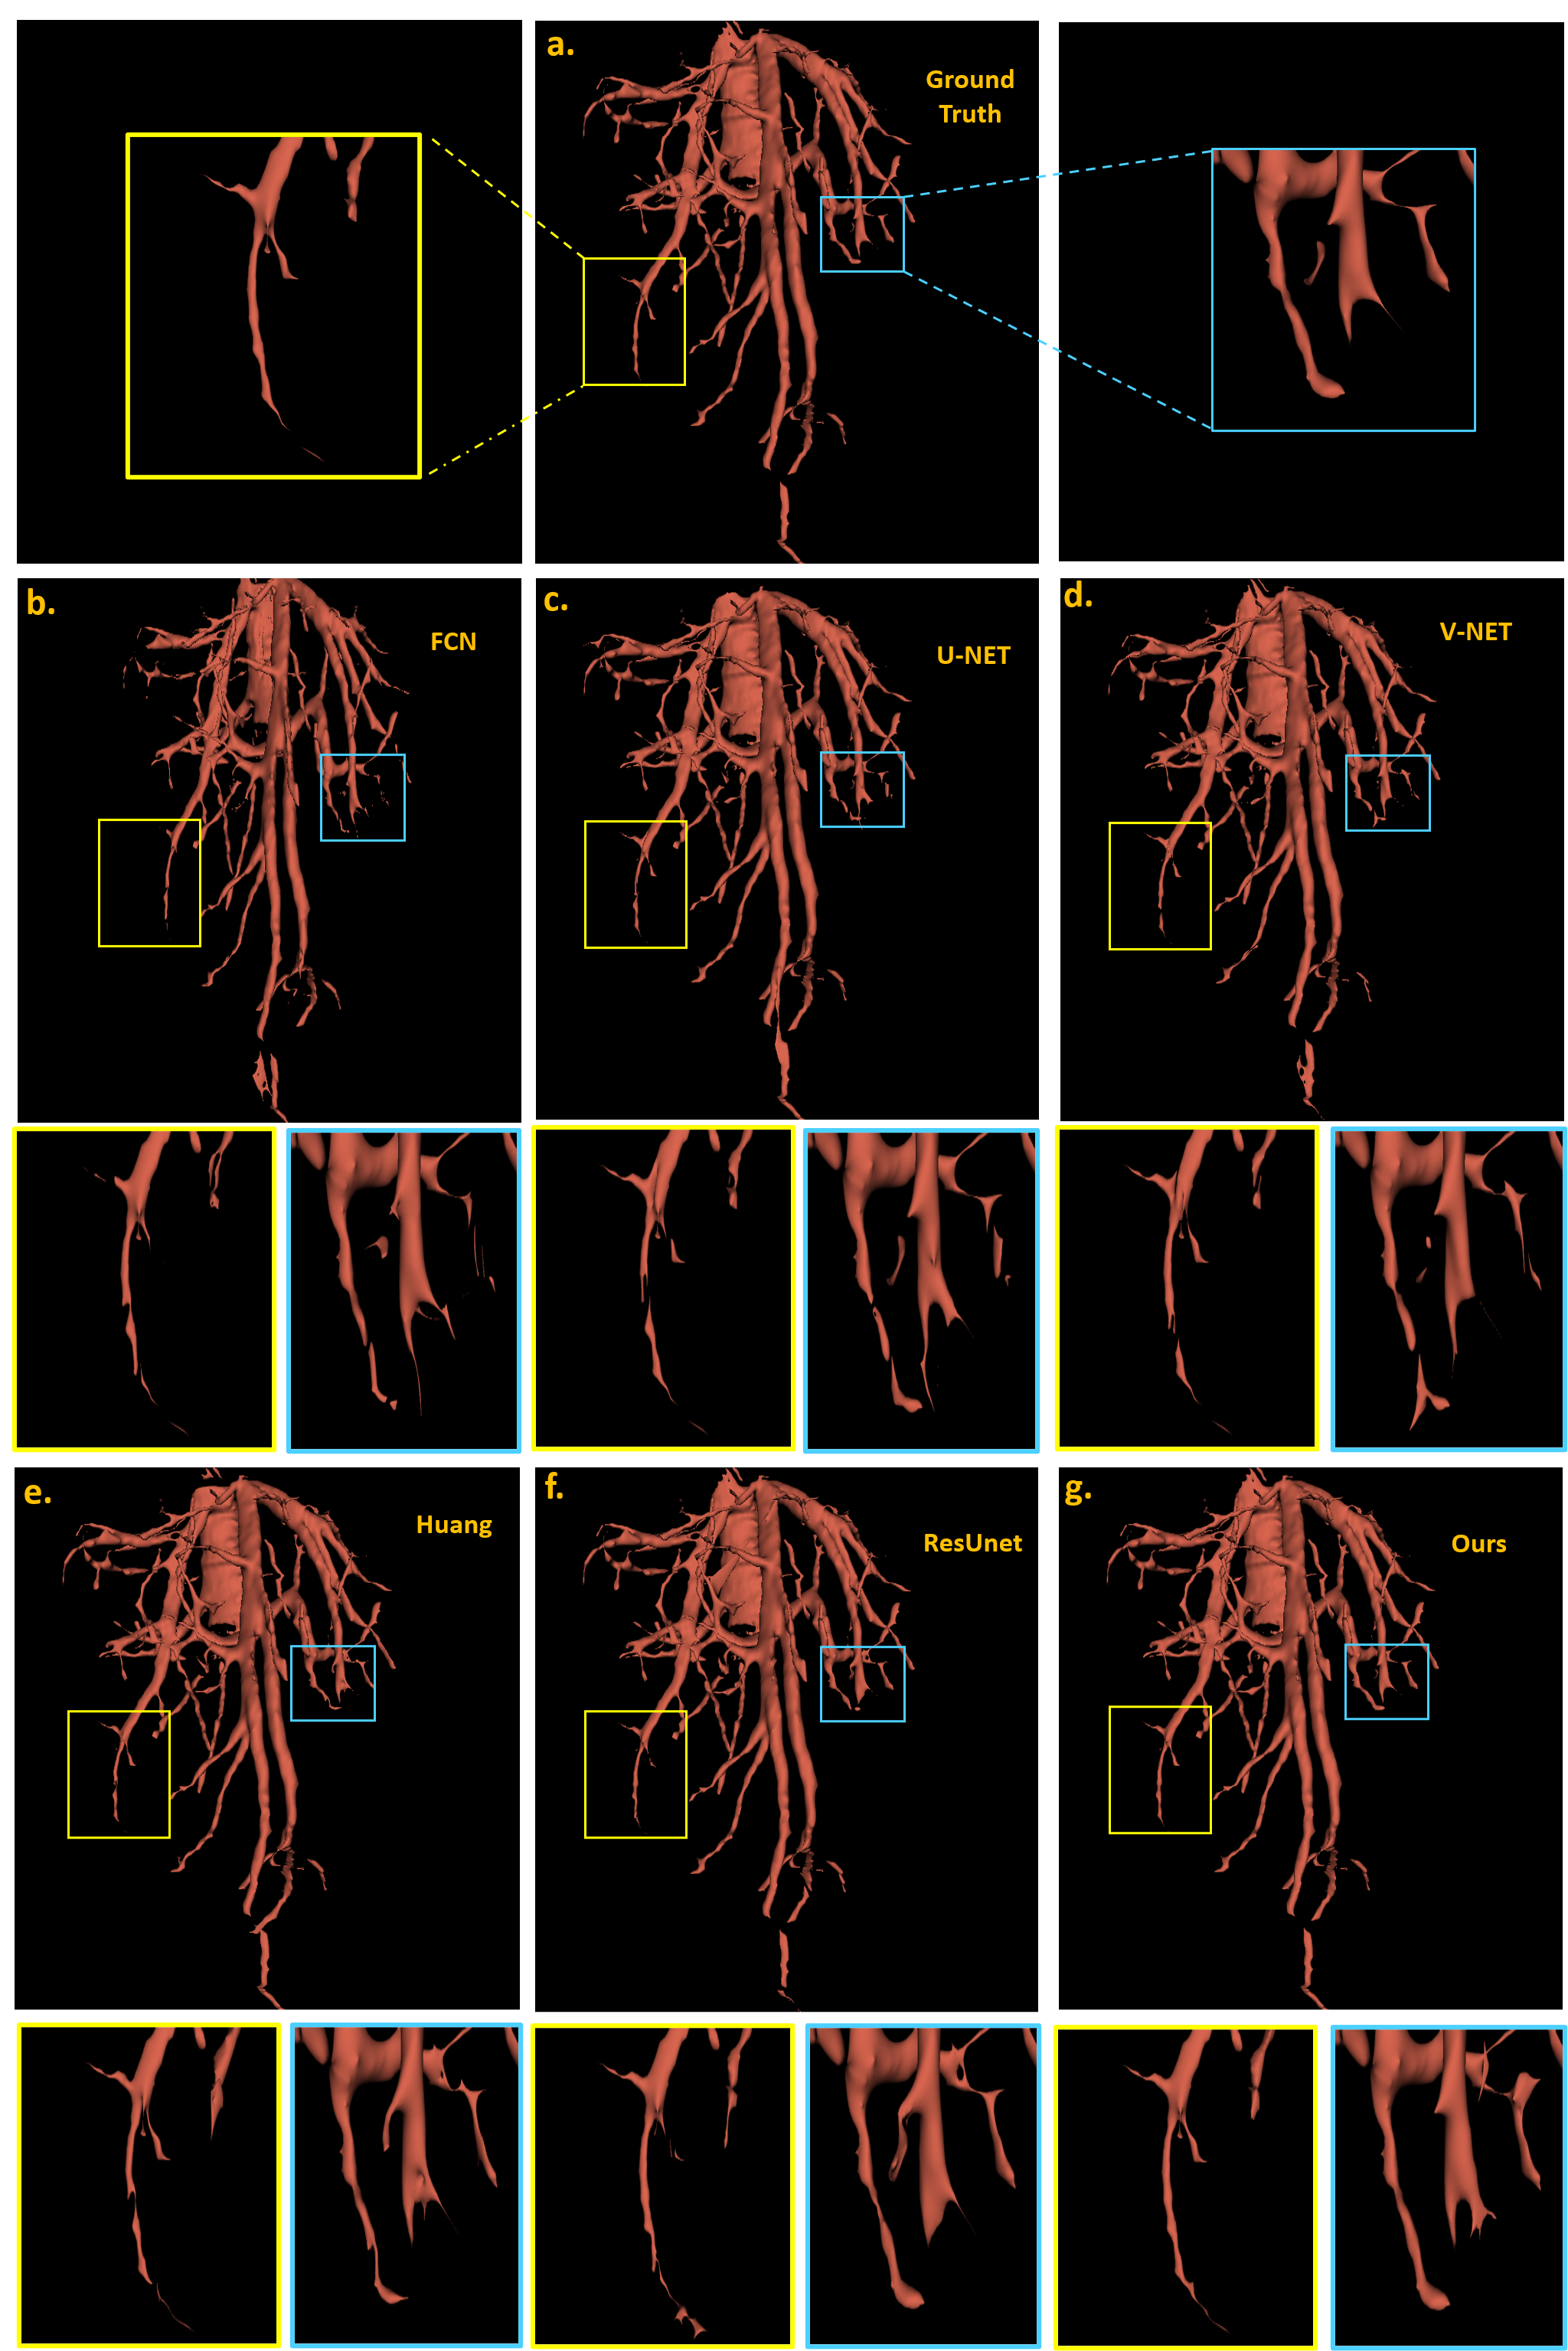

Refer to caption

Figure 4: Visualization and comparison of proposed deep learning method and state-of-art machine learning-based methods using raw volume as in put with post-processing. Three row indicates different genres methods. First row: (a) ground truth result which is most similar to our result. Second row: (b), (c), (d) the traditional 3d medical image methods. Third row:(e), (f), (g) the modern deep learning methods in the journals and our method.

Fig. 6 shows the visualization of our experiment in one complex sample. After 3D morphological close operation and post-processing, the surface of the vessels becomes smoother and some noise blocks are removed. To compare the results visually, we utilize 3D slicer’s toolbox and the zoomed-in patches. The full results are shown below in Fig. 6. This sample is long and curvy, the segmentation results of FCN and 3D U-Net,3D v-Net on hepatic veins are not so well, in which some regions are over-segmented or some minor vessel are missed. The reason could be Convolutional operators limit the capability of learning long-range dependencies. In addition, the third row’s Huang et.al and ResUnet did fairly well in the whole vessel structure, yet have many errors in the vessel edge which can be seen in the zoom-in views. By utilizing the inductive biased multi-head attention and transformer, our methods on vessels performed relatively closer to the ground truth in vessel edges and overall structure.